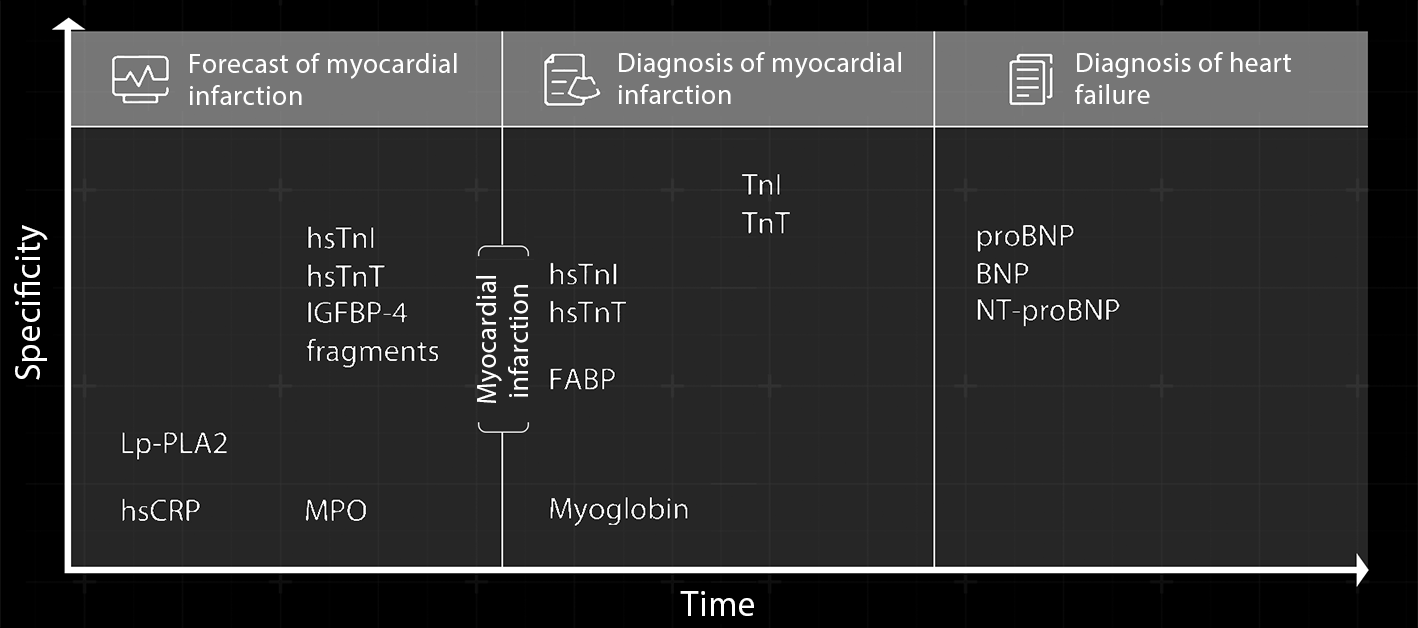

Since the 1990s, HyTest has developed a series of high-quality products for use in the forecast and diagnosis of myocardial infarction and the heart failure area, providing more valuable evidence for the companion diagnostics of cardiac diseases.

Scientists observed that after the onset of myocardial infarction, troponin is released from the heart into the peripheral circulation, and its complexes would appear in different forms over time. For over two decades, HyTest's moving increasingly close to the truth has pushed it into rethinking how to identify highly specific antibodies that can adapt to changes and deliver accurate test results.

Change of cTn forms in blood of patients with MI over time